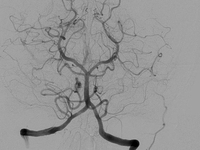

SWIFT PRIME试验表明,在急性缺血性卒中患者中,对大血管前循环闭塞的患者予以溶栓治疗和Solitaire FR(血流恢复)支架取栓术治疗可减少3个月时卒中致残率并增加患者存活比例和功能独立性。洛杉矶UCLA综合卒中中心的Jeffrey Saver博士在2015年国际卒中大会(ISC)上呈现了这些结果。

对于近端脑动脉闭塞的缺血性卒中患者(存在可挽救性组织)而言,与单独使用阿替普酶相比,采用支架取栓更能改善患者预后。这项研究于2月11日呈现在2015年国际卒中大会上,并同时在线发表于《New England Journal of Medicine》。